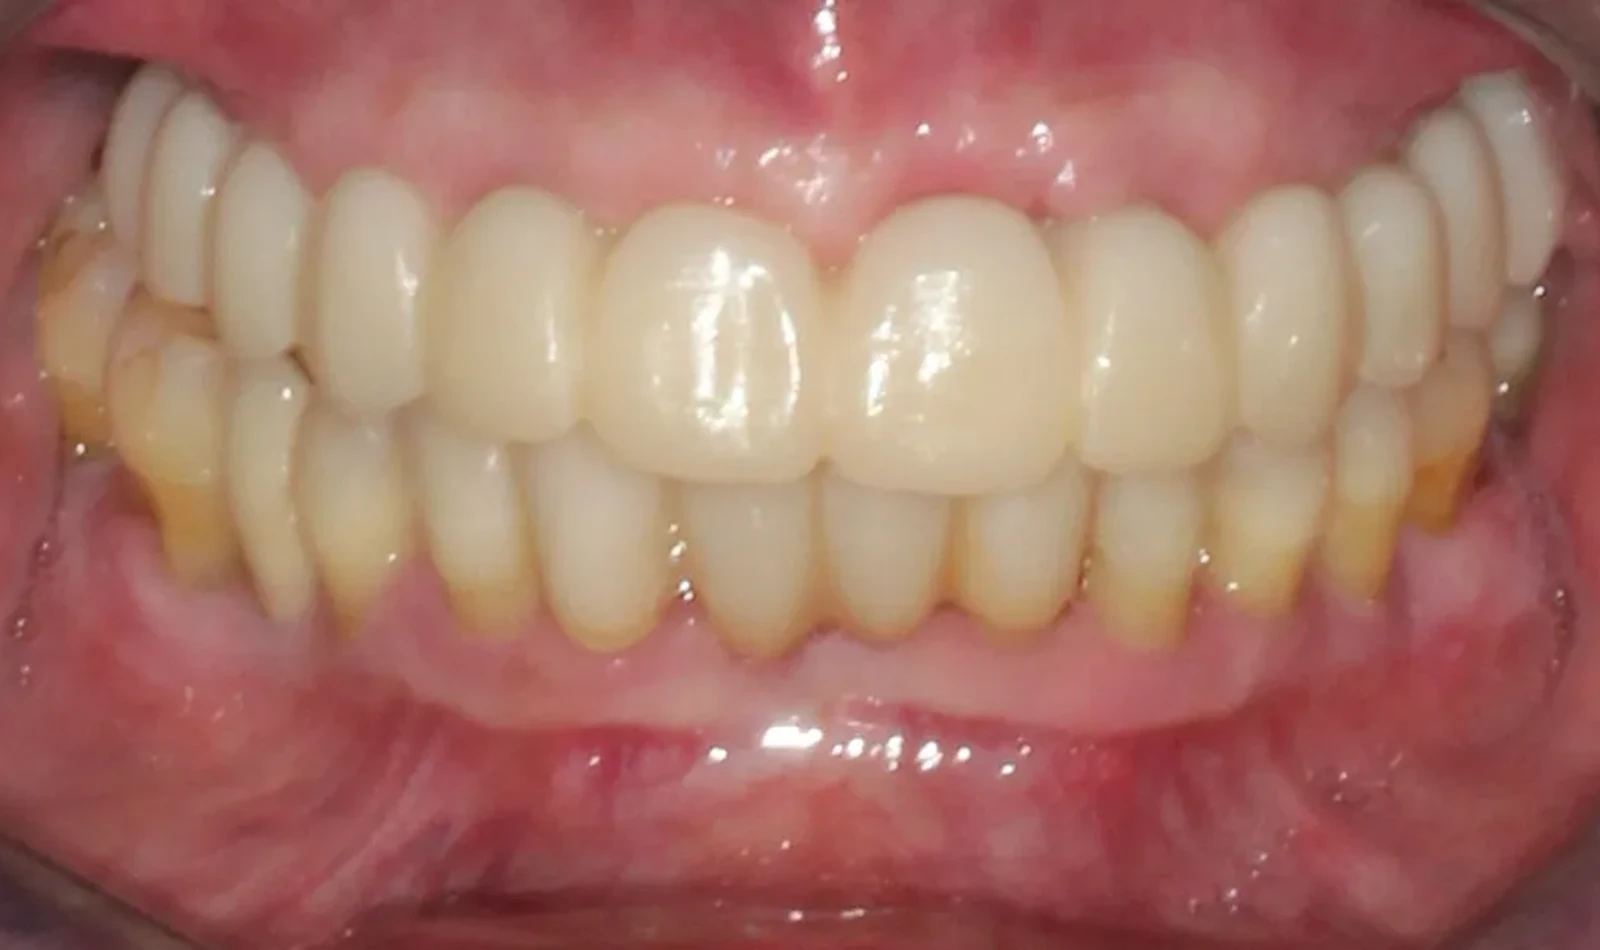

Paciente #2:

De 61 años nos visita con dientes dañados por caries y una prótesis antigua que ya no podía utilizar. Gracias a la planificación digital y la cirugía guiada, realizamos las extracciones y colocamos implantes con una prótesis fija el mismo día. Recuperó su sonrisa y la confianza de inmediato.